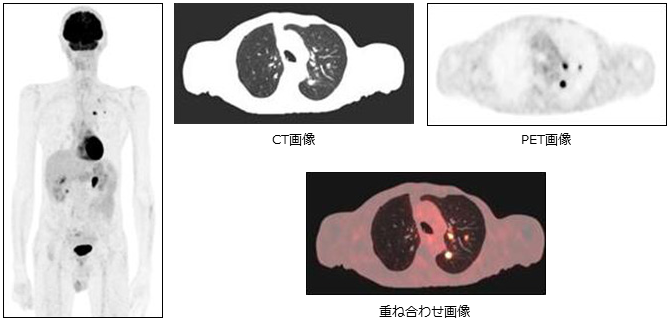

PET/CT検査

「PET/CT検査」はPET検査とCT検査の画像を重ね合わせて、疾患の性質と形態を一つの画像にすることができます。

PETとはPositron Emission Tomography (陽電子放出断層撮影)の略で、陽電子を放出する放射性医薬品を体内に投与し、その分布を特殊なカメラでとらえて断層画像を撮影する検査です。

PET検査は使用する薬剤によってさまざまな目的に利用されていますが、当院で行っているPET検査は二つあります。

一つ目は18F-FDGというお薬を用いて疾患のブトウ糖代謝を画像化する検査(FDG-PET検査)です。がんや炎症にはブドウ糖代謝が活発になる性質があり、その性質を利用して疾患の大きさや悪性度合い、転移病巣の有無、治療後の効果判定、再発の診断などが可能となります。一度の検査で全身を調べることが出来ます。薬剤によるアレルギー反応や副反応はほとんど報告されていませんが、血糖値が高いと薬剤が疾患に集まり難くなり、検査の精度が低下する可能性があります。糖尿病と診断されている方、普段から血糖値の高い方はあらかじめご相談ください。

二つ目は18F-フルテメタモルというお薬を用いてアルツハイマー病の原因物質と考えられているアミロイドβプラークが脳内に溜まっているかどうかを調べるための検査(アミロイドPET検査)です。2023年12月にアルツハイマー病による軽度認知障害の進行抑制効果が認められレカネマブというお薬が保険適用となりました。これに伴いこのアミロイドPET検査も保険適用となり、当院でも保険適用基準に従い検査を開始することとなりました。

「PET/CT検査」放射性医薬品の投与およびCT検査による放射線被ばくを伴うこととなりますが、放射線による健康被害が生じる被ばく量ではありません。

当院では健康管理センターにて「PET/CTドック」もご案内しております。詳しくは健康管理センター窓口にお問い合わせください。